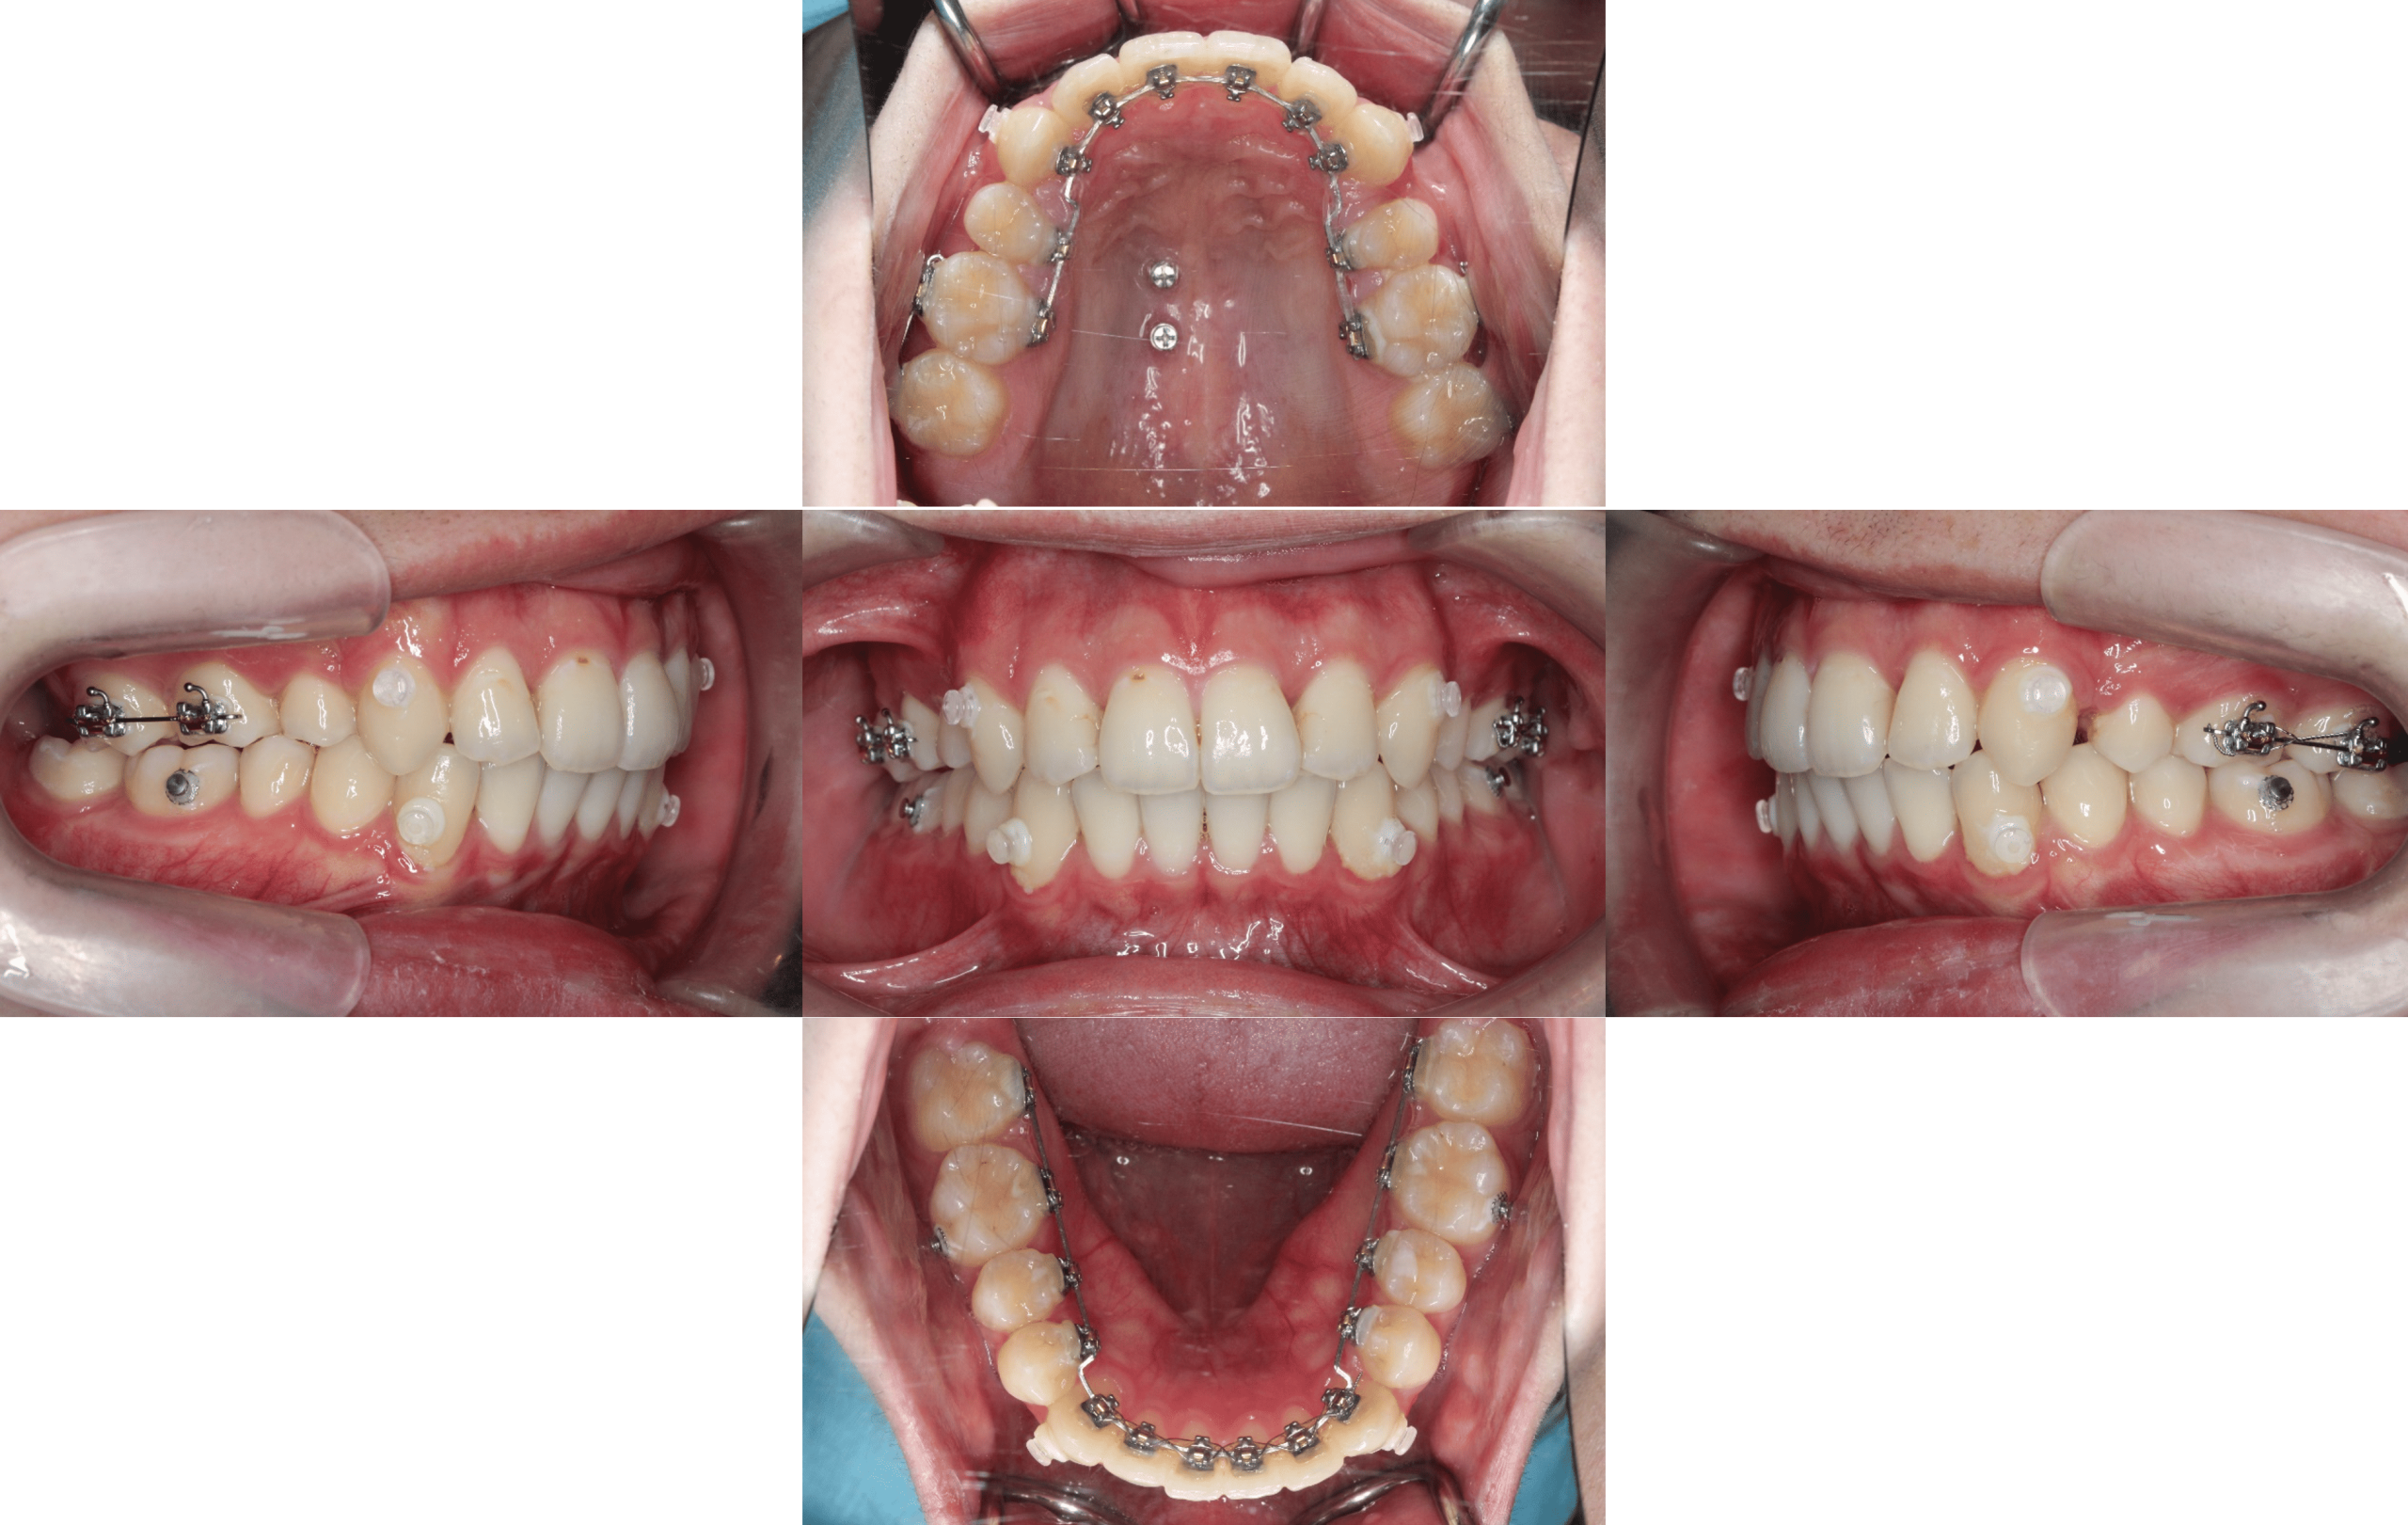

上の前歯が出ているのを治したい(通院期間1年10か月/治療回数35回)

Before

After

年齢層

20代

性別

男性

主訴

・上の歯が出ているのを治したい・右上奥と前歯のがたつき・噛み合わせが深い

治療費用

¥1,320,000

治療期間

1年10か月(治療中)

抜歯

4┴4

矯正の装置

裏側矯正(舌側矯正)

副作用、リスク

歯肉退縮,歯根吸収,疼痛,咬合の違和感,装置の違和感,虫歯,歯肉炎